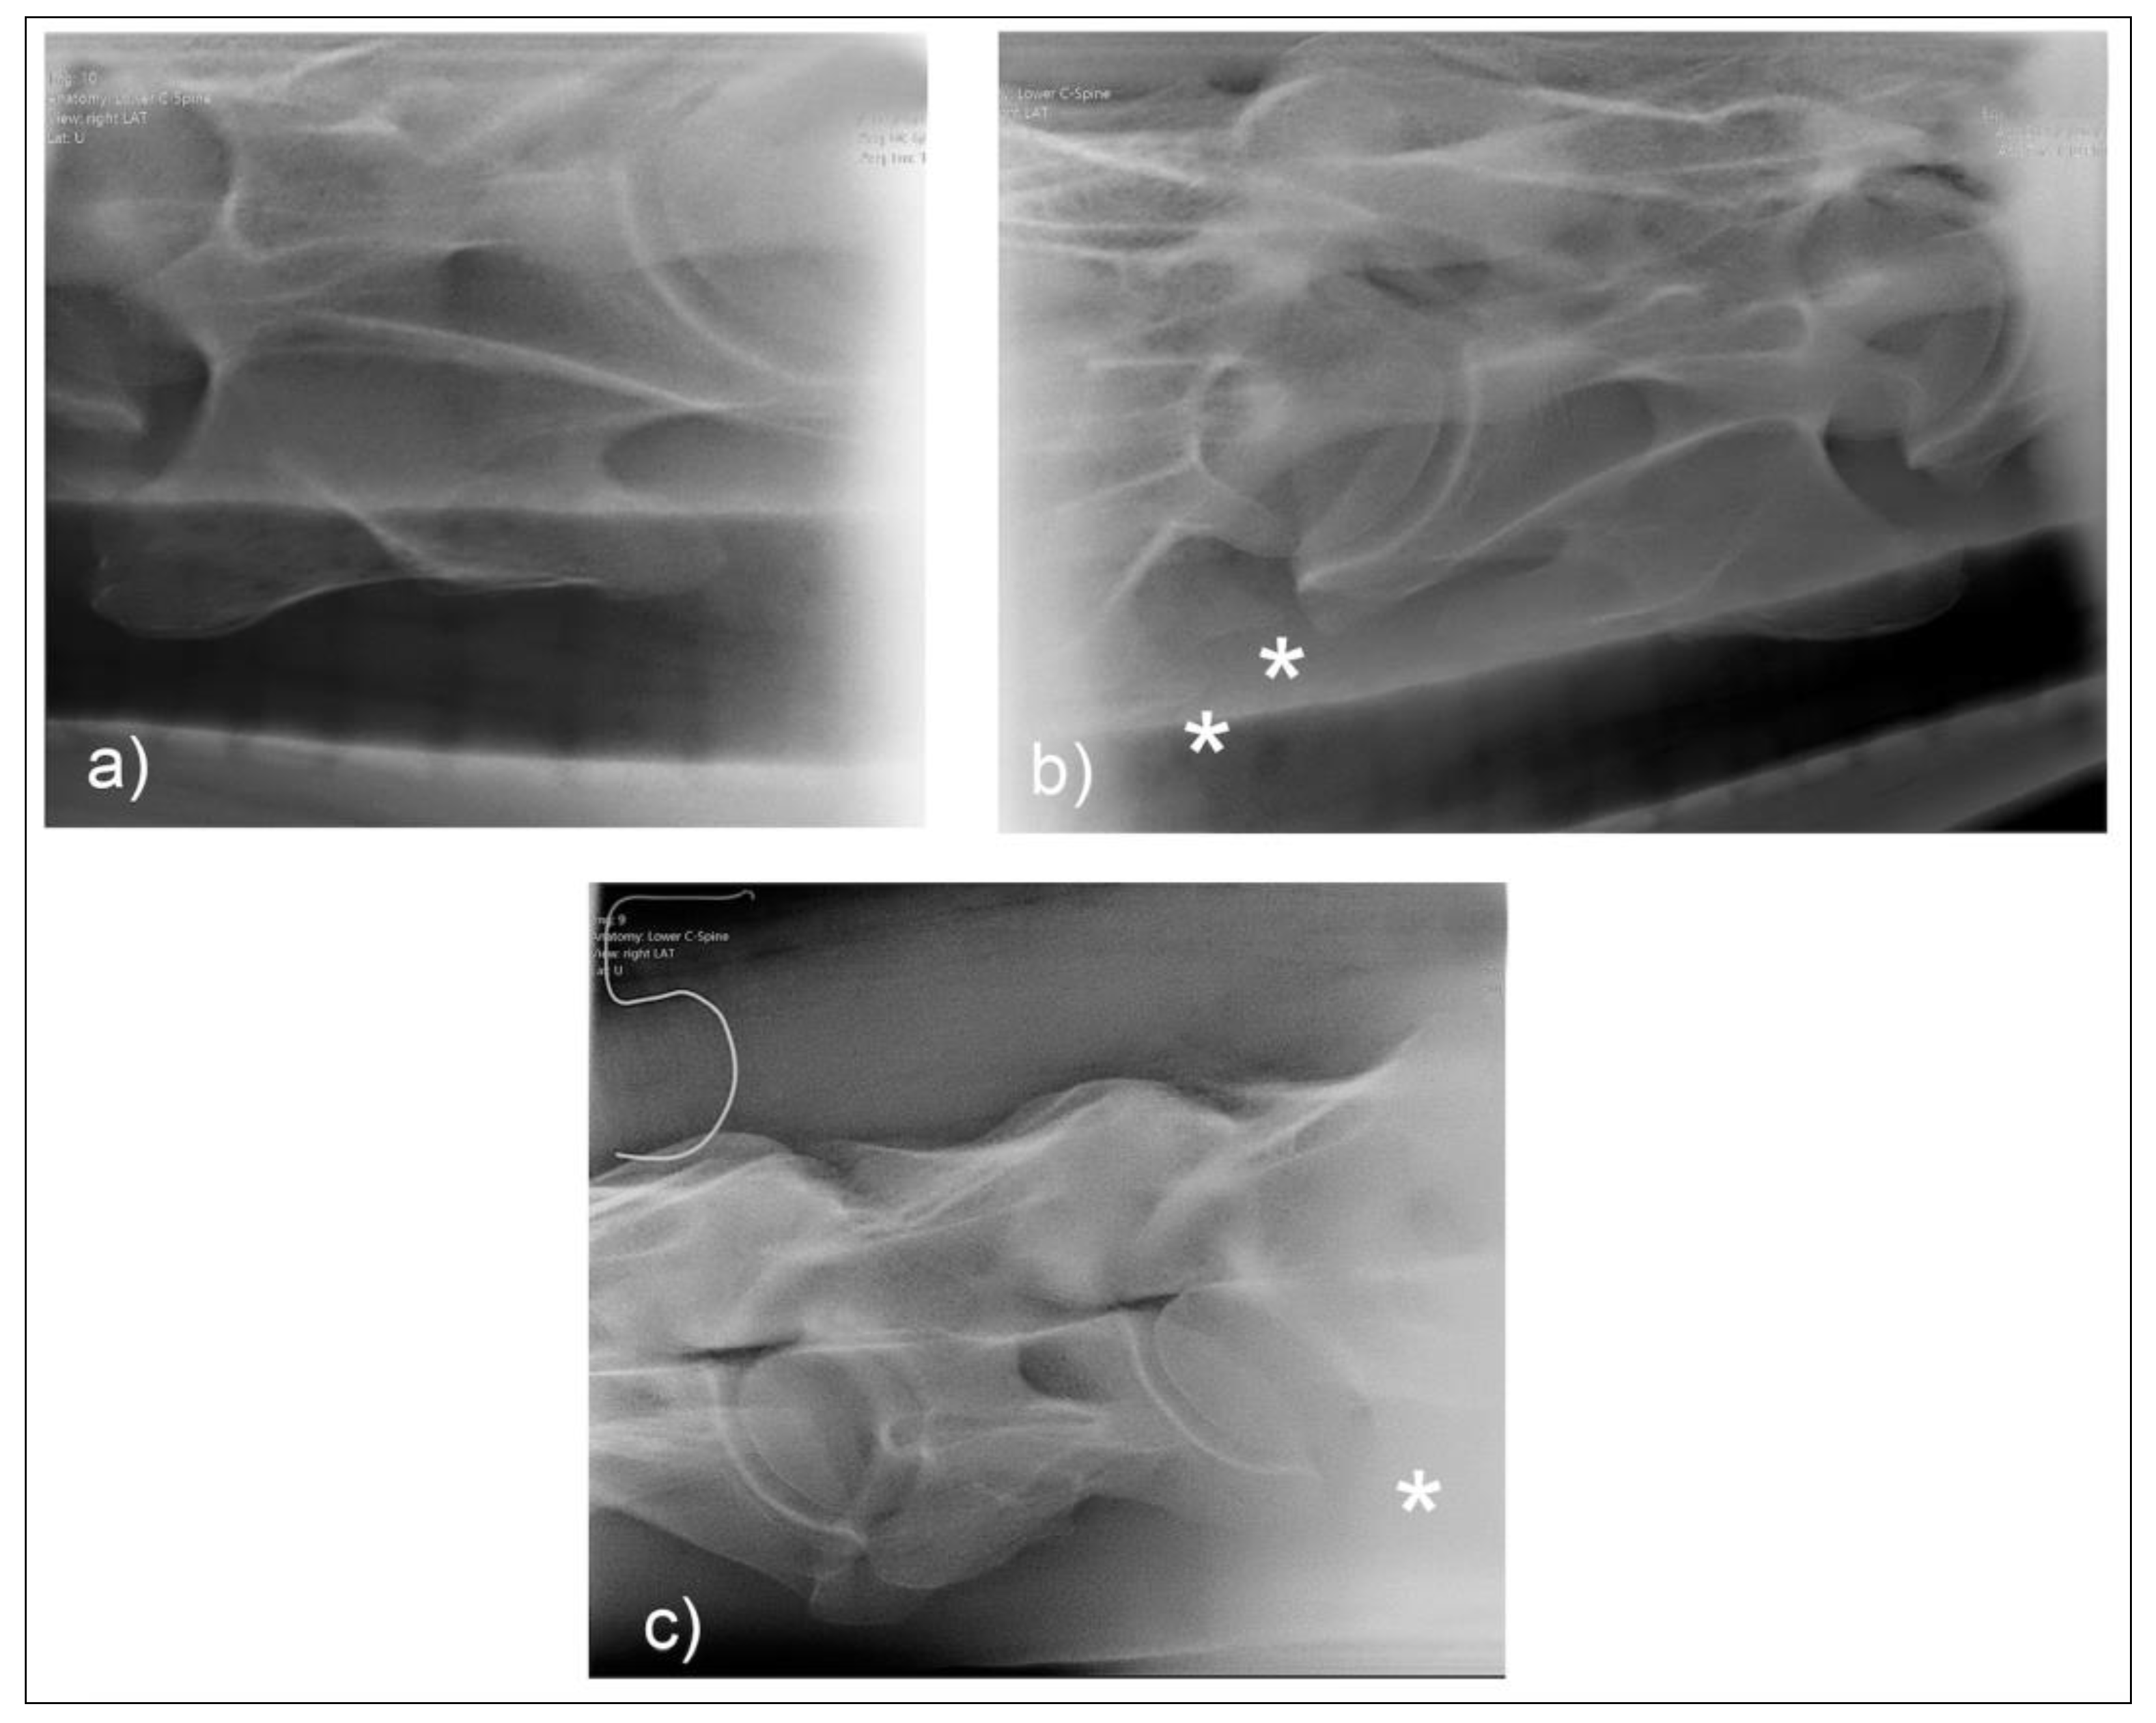

Figure 4. Normal radiographic appearance of C6 with 30° dorsal to ventral oblique right (a) and left (b). In the laterolateral view (c), the head is to the left, and both left and right ventral laminae are visible. Note the incomplete centers of ossification of the ventral laminae (*). (Images have been left in nonstandard orientation for simplicity).

For the first plate, the beam was centered on the first and second cervical vertebral articulation (C1 and C2) in a laterolateral orientation with 0° of elevation. The standard laterolateral views have been described by many authors [7,10,11]. A lateral 30° dorsal to ventral oblique highlights the lamina of C6 against the radiolucent trachea (Figure 3). Figure 4 illustrates the normal radiographic appearance of C6 using this technique.

Two common operator and reviewer errors are identification of a false bilateral morphologic variation of C6 when actually imaging the normal C5 vertebrae. Conversely, diagnosing the bilaterally absent ventral laminae on C6 as normal is another common mistake (Figure 10c). It should be noted that the caudal ventral tubercles of C6 have separate centers of ossification that may be misdiagnosed as fractures [7]. Asymmetry of the articular process joints in the cervical spine may make true laterolateral image capture difficult [7]. The laterolateral images of C6, along with the dorsal to ventral oblique images, are key to interpreting the symmetry, length, and shape of the lamina (Figure 4c). Field radiographs make the assessment of transposition on to C7 difficult in some cases. The transposition may be visible less commonly on the oblique views (Figure 9b) depending on the shape and position of the transposition [11]. Transposition on to C7 is more commonly seen on the laterolateral views and is usually seen below the transverse processes [11]. In some cases, the transposition may be seen on the oblique view (Figure 9b). Some three-dimensional alterations are so severe that misinterpretation of the morphology on C7 can occur (Figure 8c). This highlights the need for more detailed diagnostic assessment in these cases. Spinal cord compression by an asymmetrical canal, articular process periarticular bone formation and extent of intravertebral foramina compression cannot be assessed by radiography alone [10]. The study of the prepared vertebra in three dimensions is key to understanding the potential alterations in regional biomechanics.